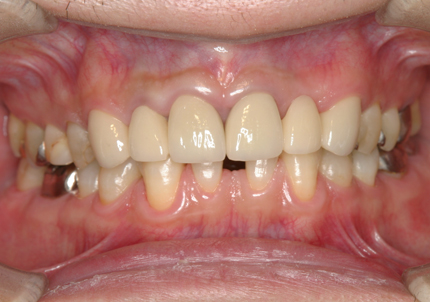

患者:Y.S 様

初診日 :2018年10月

主訴 :上顎前歯部審美障害、臼歯部補綴治療

1.初診時口腔内写真(2018年10月)